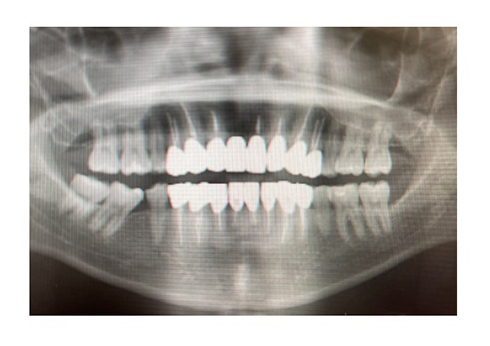

痛みが引いた後も違和感が続いたため、歯科でレントゲンを撮ってもらったところ、「ジルコニアは硬いから割れないかわりに、逆に土台の自分の根本の歯に衝撃が来て、中で土台の歯が割れる事がある」と、歯の土台が割れている可能性を告げられたとのこと。アレンさんは「ブリッジ自体が難しくなる上に、入れていたジルコニアも、支えがないから再度入れられない事になるし、土台となる根本がなかったら、もはやジルコニアすら被せられない」と、自身の歯が“笑えない事態”に陥ったことに大打撃を受けた様子でコメントしていました。

歯を巡る受難は終わらず、何軒かの医師を訪問したところ、新たな問題点まで浮上。16本の歯を入れ替えた際に形成した土台部分が大変浅かったといい、「土台が見えないけど土台はもちろん入れてもらってるよね?」「何でこれを執刀した医師はこんな浅く入れたんだろう」などと首をかしげられたといいます。